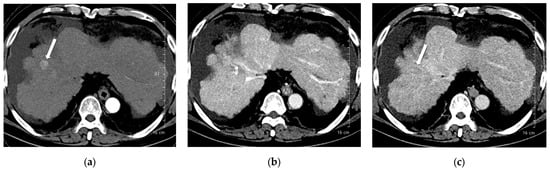

A total of 168 focal liver lesions were identified in 93 participants (80 lesions in the high-concentration iodine group [n = 47] and 88 lesions in the low-concentration iodine group [n = 46]). Lesions comprised HCCs (n = 80), adenocarcinomas (n = 14), dysplastic nodules (n = 15), hemangiomas (n = 33), and regenerative nodules (n = 3). Lesion size was equivalent between the high- and low-concentration iodine groups (14.36 ± 14.72 mm versus 17.50 ± 12.27 mm, p = 0.134). Per-lesion detectability showed no significant difference between the groups (0.862 versus 0.909, p = 0.18; Table 6). Among detected lesions, the mean conspicuity score was significantly higher in the LCIC group than in the HCIC group (4.41 versus 4.07, p = 0.002) (Figure 3, Figure 4, Figure 5 and Figure 6).

Figure 4. A 55-year-old man with hepatocellular carcinoma (HCC) on magnetic resonance imaging, characterized by diffusion restriction, high signal intensity on T2-weighted images, and washout. CT was performed using high-concentration iodine contrast material (total iodine dose, 584.14 mg I/kg). Overall image quality in the arterial and portal phases was acceptable. (a) A 7-mm enhancing nodule (arrow) is visible on the arterial phase at 100 kVp; (b,c) The nodule is inconspicuous on the portal and delayed phases. Both reviewers classified the lesion as benign (LI-RADS category 3).

Figure 5. A 56-year-old man with hepatocellular carcinoma (HCC). CT was performed using low-concentration iodine contrast material (total iodine dose, 389.89 mg I/kg). Overall image quality in the arterial and portal phases was unacceptable (mean scores < 4): (a) A 17-mm enhancing nodule (arrow) is visible on the arterial phase at 120 kVp; (b) The nodule shows subtle washout on the portal phase (arrow); (c) The nodule is inconspicuous on the delayed phase. The two readers classified the lesion as LI-RADS 4 and LI-RADS 3, respectively.